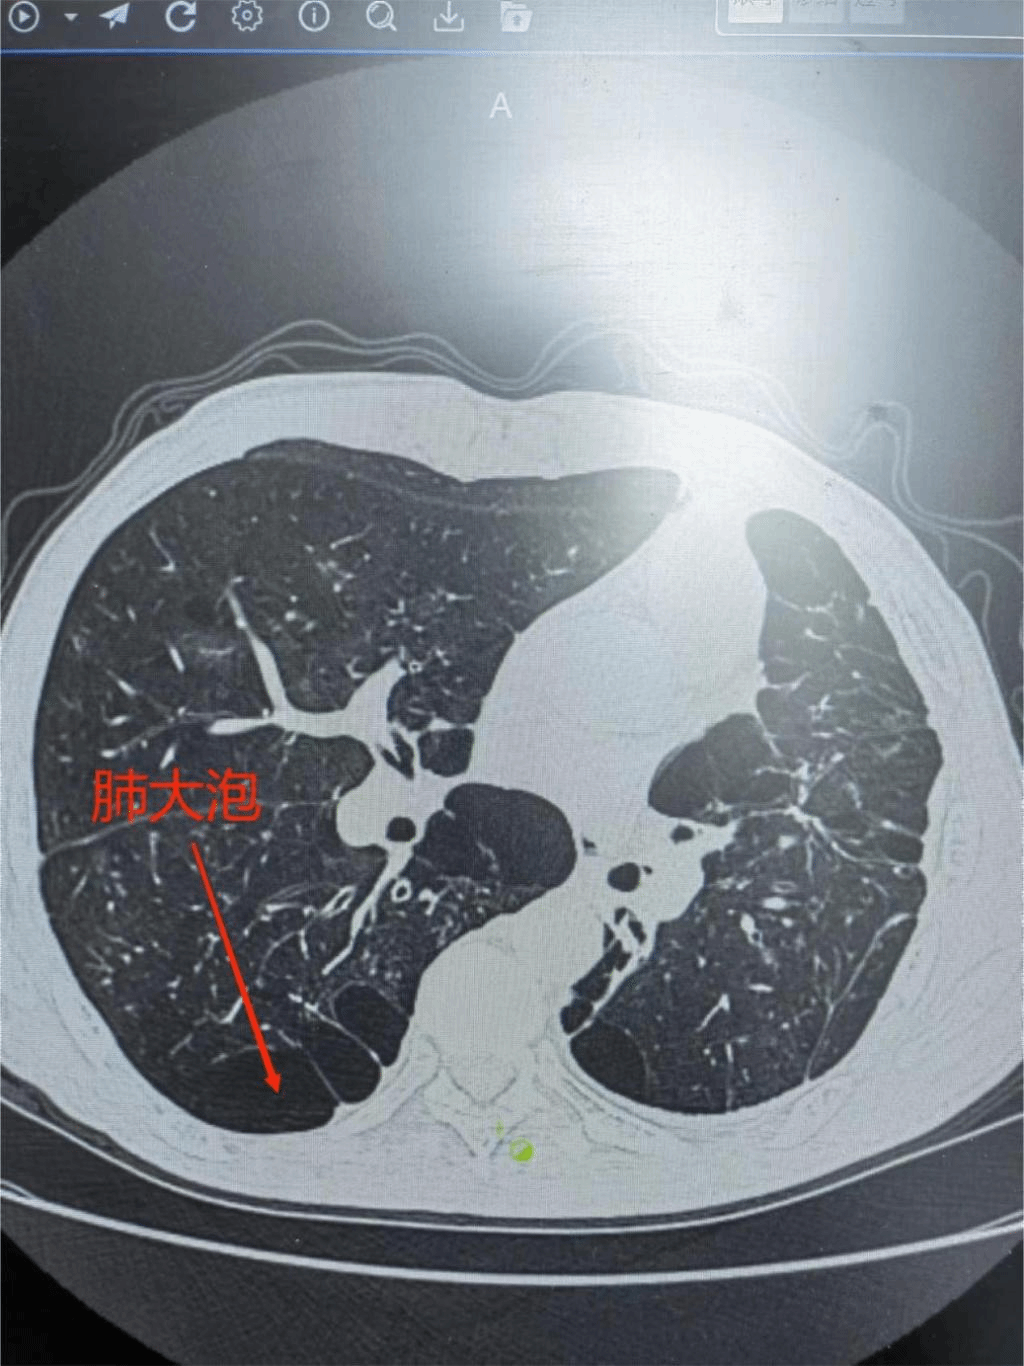

1月29日BB贝博艾弗森官方网站第二附属医院呼吸内科付云杰主任团队在胸外科张毅博士、麻醉科李成涛主任的协助下,成功为一例重度慢阻肺患者成功实施经无痛支气管镜双肺EBV活瓣肺减容术,一次性为患者处理了双侧肺大泡。术后患者即可起床活动,饮食照常,完全无痛,胸闷、气喘症状得到明显缓解,效果立杆见影。这是我院第二例支气管镜单项活瓣肺减容术,也是九江地区首例双肺支气管活瓣肺减容术。标志着我院支气管镜介入技术迈入新台阶,将造福更多九江乃至周边区域的患者!